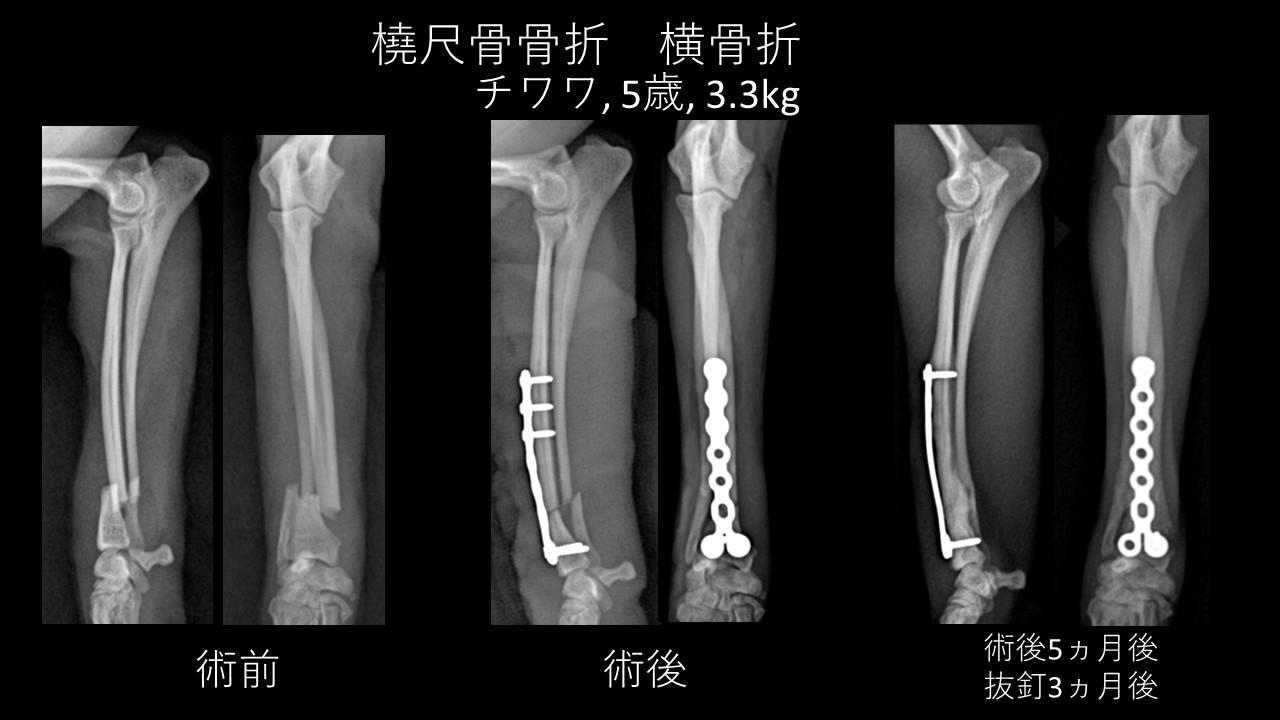

- 整形外科は骨折やTPLOなどの手術に対応しています。

骨折